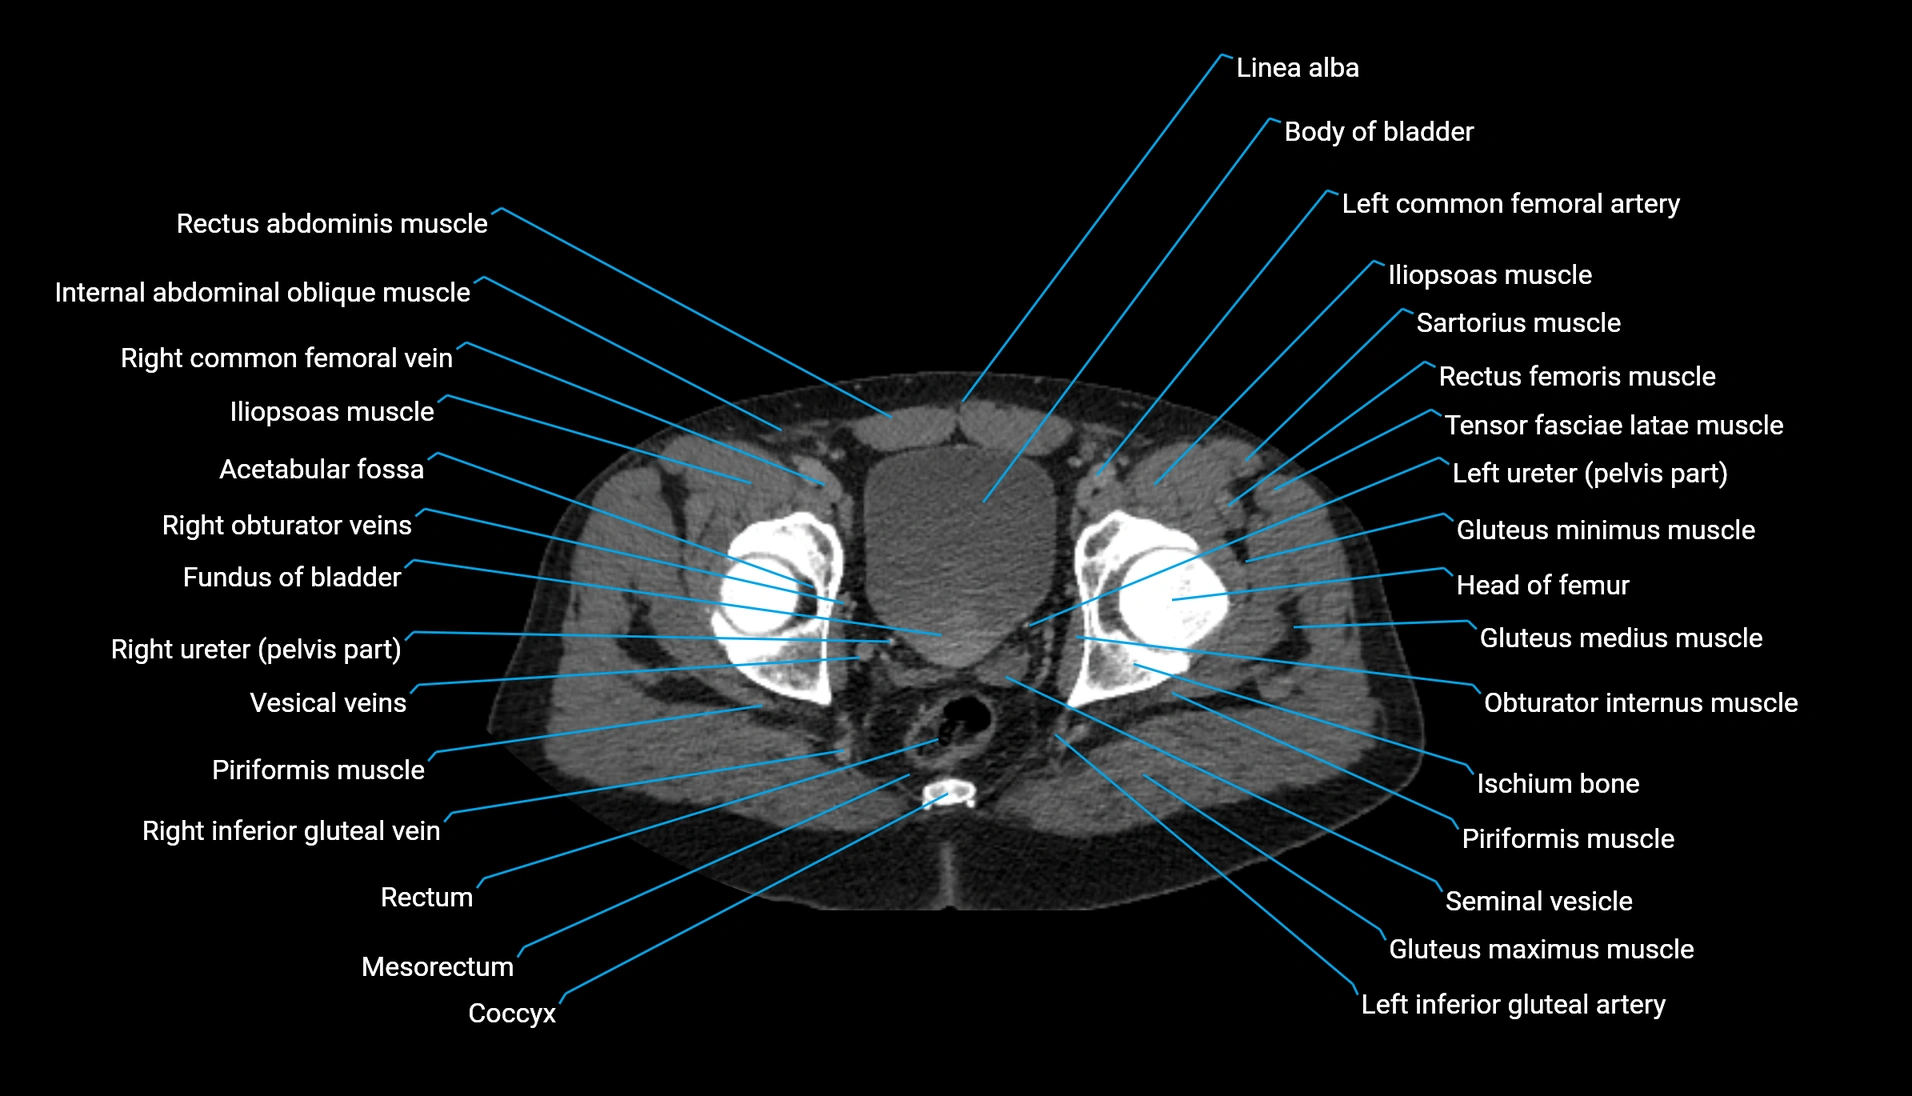

CT Appearance

Non-contrast CT:

-

Demonstrates cortical bone of acetabular rim in excellent detail

Detects fractures, dysplasia, retroversion, or bony overcoverage (pincer impingement)

3D reconstructions used in preoperative hip surgery planning

CT VRT 3D image

CT image